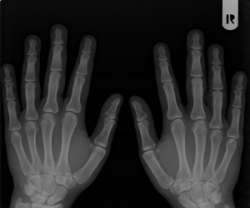

Reumatoidná artritída

Reumatoidná artritída (RA) je chronické, dlhodobé zápalové ochorenie postihujúce najmä kĺby, ktoré vzniká preto, že imunitný systém nefunguje tak, ako by normálne mal fungovať. Väčšinou si imunitu spájame s obranou proti infekciám. Imunitný systém ľudí postihnutých reumatoidnou artritídou v boji s infekciami zároveň napáda vlastné tkanivá a bunky a poškodzuje ich. Preto sa reumatoidná artritída označuje aj pojmom autoimunitné ochorenie.

Ako sa prejavuje reumatoidna artritída?

Bolesť kĺbov je jeden z najčastejších príznakov reumatodinej artritídy. Sprevádza ju zvýšená teplota kĺbov, začervenanie a opuch kĺbov. Tieto príznaky sa väčšinou objavujú symetricky — na obidvoch stranách tela. Ďalším bežným príznakom je stuhnutosť kĺbov, najmä ráno. Všetky tieto príznaky sa menia v závislosti od stupňa závažnosti ochorenia. Sú prejavom postihnutia kĺbov a ak ostane ochorenie bez liečby, môže vyústiť do ich deformovania. Preto je veľmi dôležité diagnostikovať reumatodinú artritídu čo najskôr.

Reumatoidná artritída je progresívne ochorenie, čo znamená, že bez správnej liečby príznaky ako zápal môžu viesť k trvalému poškodeniu kĺbov. S progresiou kĺbového poškodenia môže potom dôjsť k deformitám kĺbov, strate ich funkčnosti a celkovej nízkej kvalite života.

Presná diagnóza je veľmi dôležitý krok pre ďalšie zvládanie ochorenia. Na stanovenie diagnózy reumatoidnej artritídy potrebuje lekár urobiť anamnézu, fyzikálne vyšetrenie, krvné testy, röntgenologické vyšetrenie a iné špeciálne vyšetrenia.

Podrobné fyzikálne vyšetrenie je najvýpovednejšie vyšetrenie pre diagnózu RA. Sleduje sa každý kĺb, výskyt opuchu, bolesti pri pohybe, obmedzenie pohybu a dlhodobé poškodenie. Podľa počtu postihnutých kĺbov sa určuje stupeň závažnosti ochorenia a jeho prognóza.